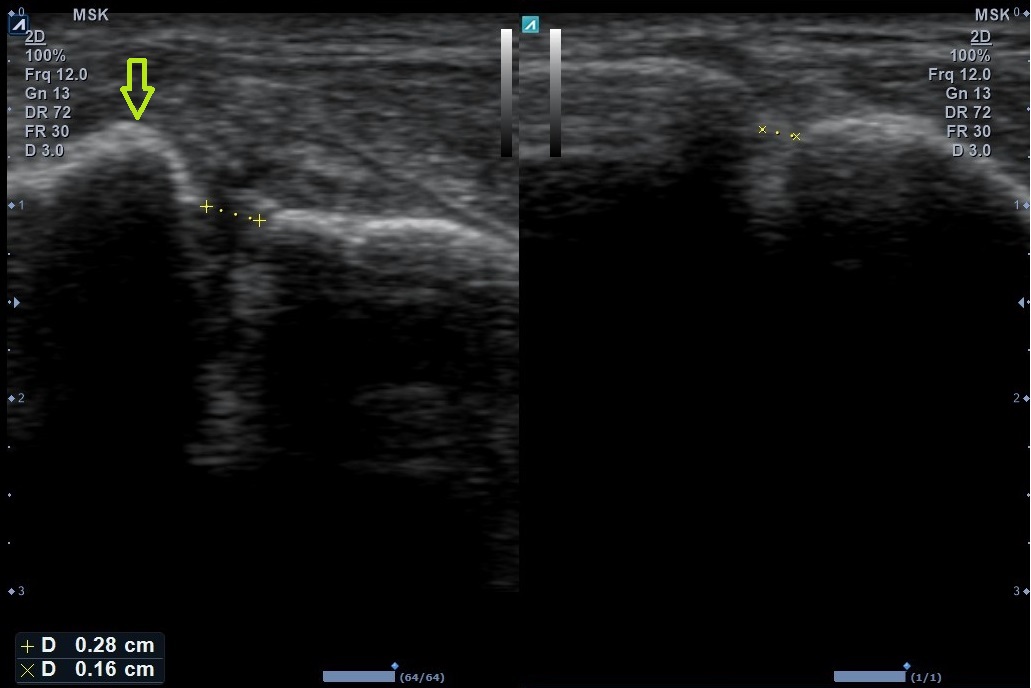

Klasické rtg projekce, ideálně se zatíženou DK, mohou odhalit zlomeninu nebo rozestup kostěné „vidlice“ (tibie a fibuly) při poruše syndesmózy. Je možné řídit se normativními hodnotami nazývanými jako tibiofibulární clear space a mediální clear space, které by měly být ≤ 6 mm (Obr 3). Vazivový aparát syndesmózy však na rtg přímo viditelný není a případný rozestup tibie a fibuly je pouze sekundárním ukazatelem s omezenou schopností odhalit subtilnější zranění. Z naší zkušenosti vyplývá, že tyto rozměry často ani hodnoceny nejsou a popis rtg snímků zraněného hlezna je většinou omezen na informaci o přítomnosti/nepřítomnosti defektu na skeletu. Vedle toho byla prokázána jen slabá korelace mezi měřením hodnot clear space  z rentgenových snímků a potvrzenými úrazy syndesmózy na MRI. (5) Naopak vyšetření syndesmózy na MRI prokazuje vysokou shodu mezi různými vyšetřujícími i vysokou senzitivitu a specificitu v porovnání s artroskopickými nálezy. Pomocí MRI však není možné provádět projekce se zatížením DK. Jako dobré řešení se jeví sonografie – pomocí diagnostického ultrazvuku můžeme zhodnotit klíčové komponenty syndesmózy a provádět dynamická vyšetření, tj. např. při zevní rotaci hlezna a vyšetření se zátěží DK. Důležité je i porovnání s druhostrannou končetinou. Diagnostickým ultrazvukem však ne vždy poznáme kostní zranění nebo osteochondrální léze, které mohou být přidruženy. Proto je vhodná kombinace s rtg. Můžeme však zaznamenat novotvorbu kostní hmoty ve smyslu přítomnosti osteofytů či heterotopických osifikací, tj. častých příčin dlouhodobé bolesti a dysfunkce regionu.

Obr. 4, Ultrazvukový nález roztržené syndesmózy vlevo ve srovnání se zdravou pravou stranou; zřetelné porušení mezikostní membrány s tekutinou (tekutina hypoechogenní = tmavá); za povšimnutí stojí i rotace fibuly (žlutá šipka) a zvětšení mezikostního prostoru, tj. rozestup kostí zřetelný i v této projekci, kdy nebyla DK zatížena; zdroj: archiv naší ambulance, zveřejněno se souhlasem pacienta; (kliknutím se zvětší)